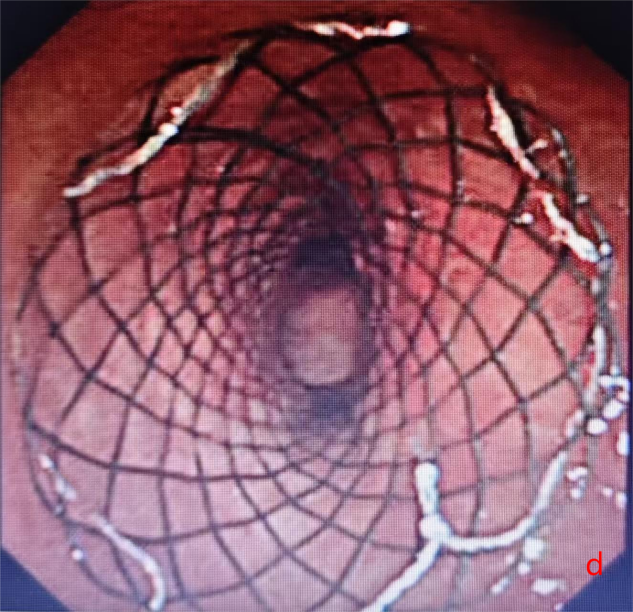

面对凶险的气道梗阻情况,温岭市第一人民医院呼吸与危重症医学科团队迅速展开全面评估。李相国主任医师和李康副主任医师认为,经支气管镜气管支架植入术是当下最适合的治疗方案——这项技术无需开胸,创伤小,能精准解决气道梗阻问题,为后续治疗争取时间。

2025年10月10日,手术在全麻下顺利开展。医护团队通过支气管镜的精准引导,将支架成功植入患者气管狭窄部位,整个过程平稳有序。术后奇迹很快显现:W先生的呼吸困难症状当场明显缓解,复查胸片提示气道下段通畅度显著改善,没过多久便能正常进行日常活动。短暂恢复后,他顺利返回继续接受胸部肿瘤放疗,整个放疗过程进展顺利,胸部肿瘤明显缩小。